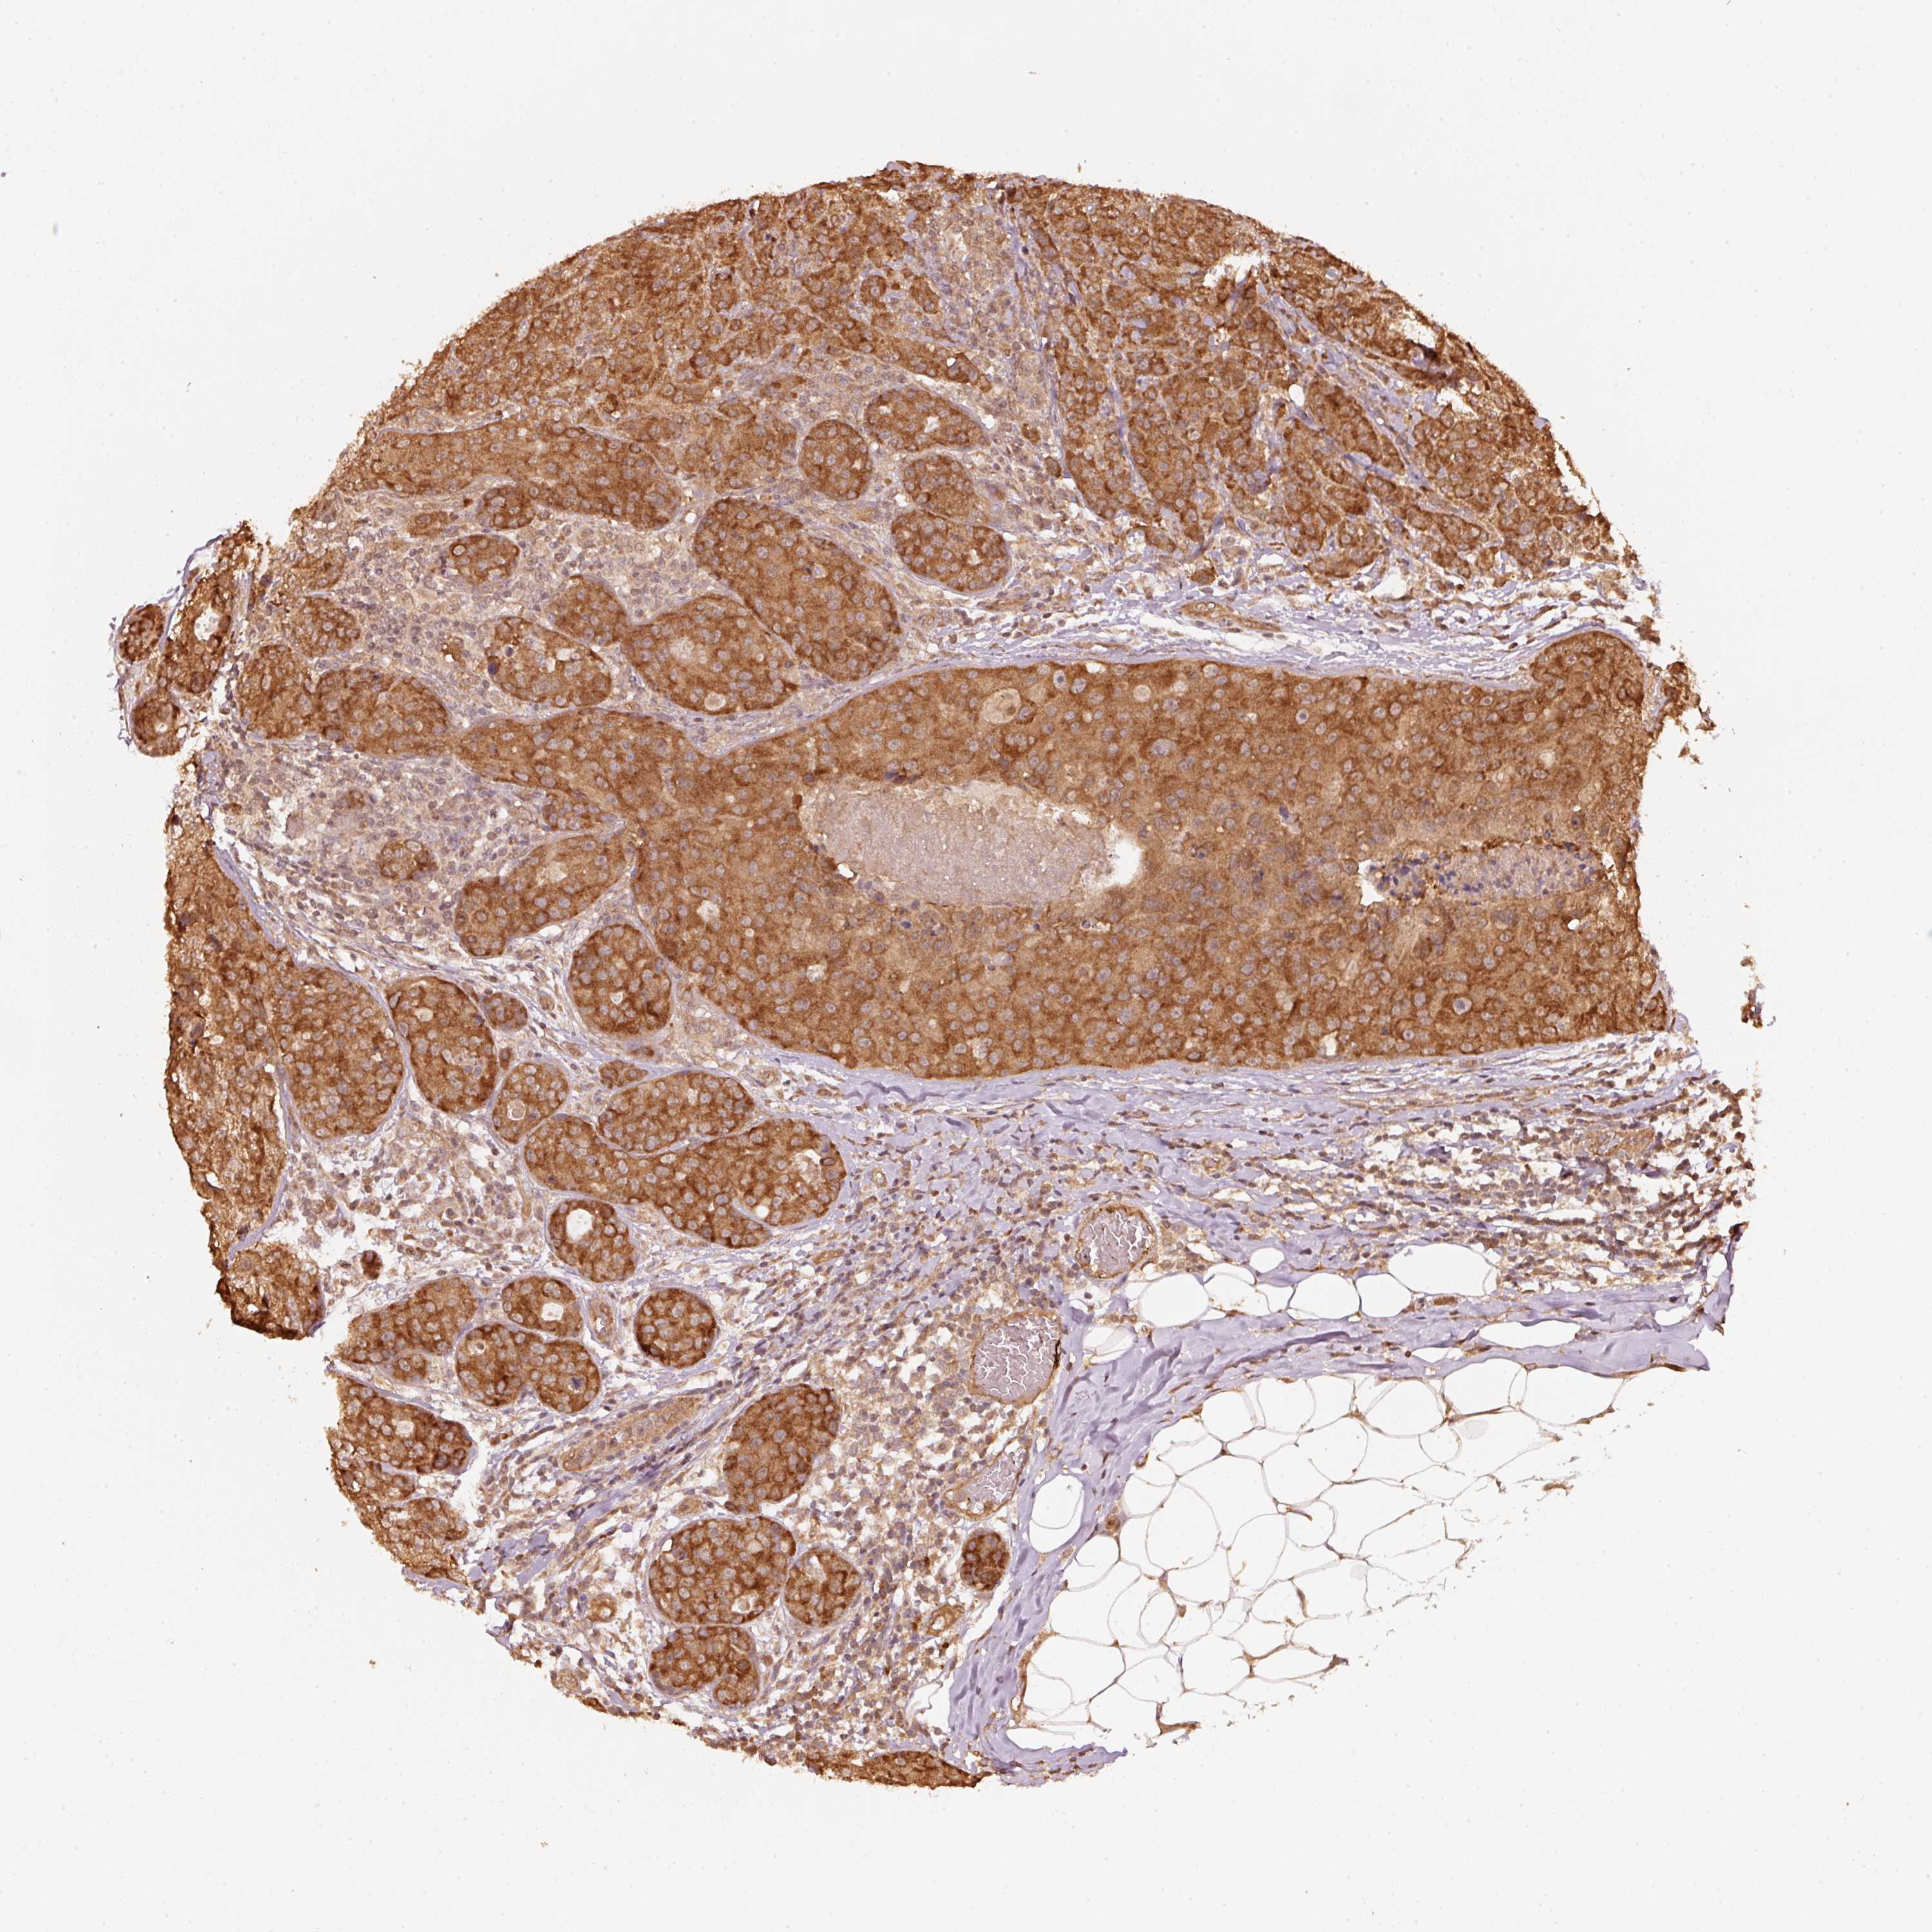

CANCER BREAST CANCER Show tissue menu

BRCA TCGA BRCA VALIDATION PROTEIN EXPRESSION